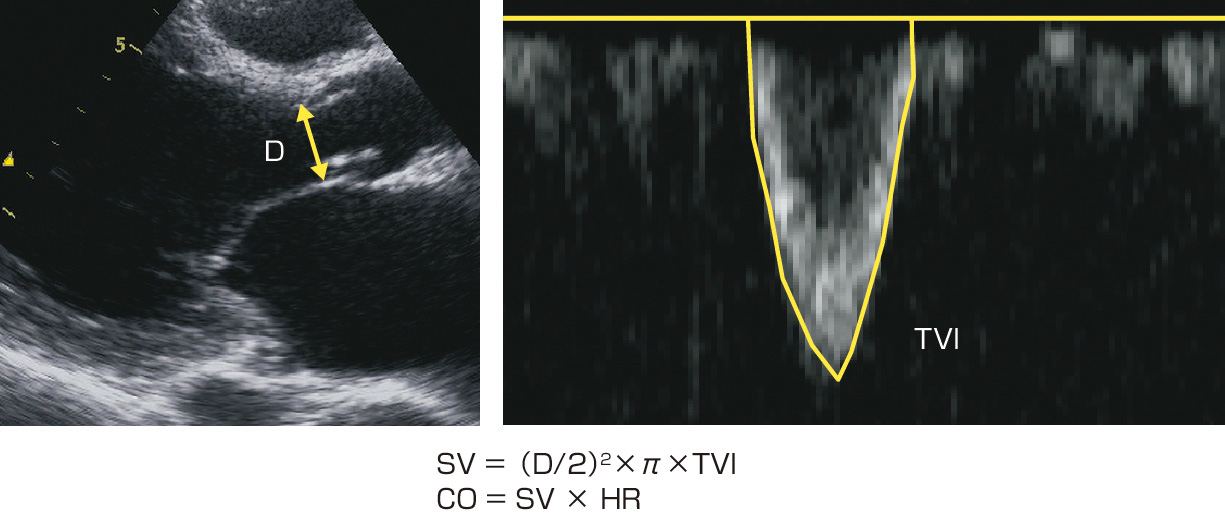

ⓔ図8-5-19 1回拍出量,心拍出量の計測 D:大動脈弁輪径,TVI:左室流出路血流速の時間速度積分値,SV:1回拍出量,CO:心拍出量,HR:心拍数.